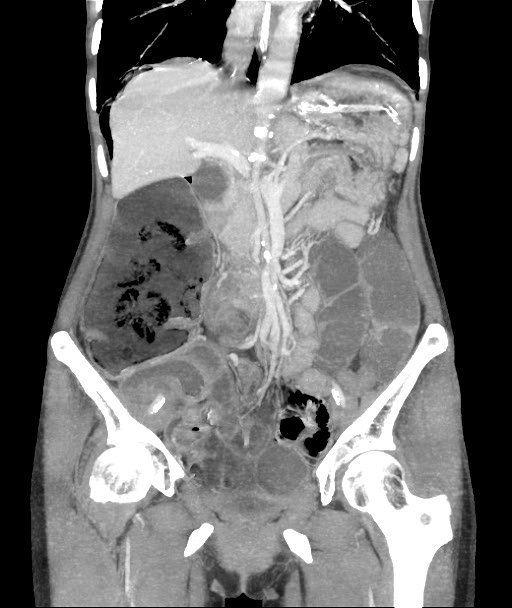

CECT Abdomen: F/S/O Acute Intestinal Obstruction (transition point in transverse colon) with minimal free fluid in pelvis with pneumoperitonium with few air foci in the wall of ascending colon Pneumatosis intestinalis

Cause Midgut volvulus

Adhesion Band

Figure 2: Cect Showing Features of Intestinal Obstruction